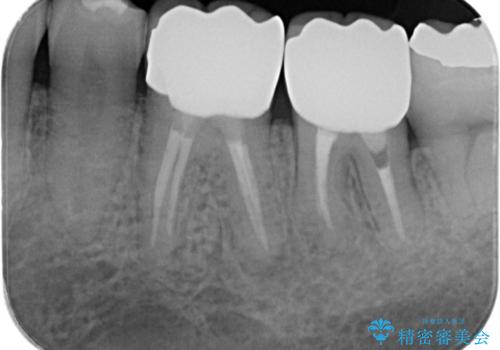

- 銀歯・虫歯・治療途中の歯を治していきたい、セラミックの歯にしたい!と希望され来院されました。

銀歯の下で再発した虫歯や、根尖病変等、多々の問題が認められましたがひとつづつ丁寧に改善し、長期的な予後の見込めるセラミック治療を行っていきます。